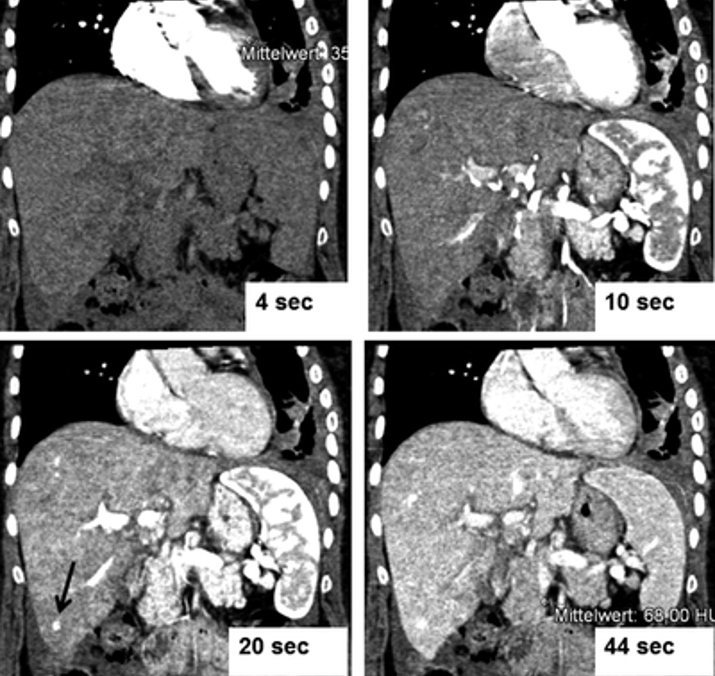

Mithilfe ultraschneller Bildgebung eines High-End-Computertomografen kann an der Klinik für Diagnostische und Interventionelle Radiologie gezielt die Durchblutung von Organen dargestellt werden.

Diese moderne Bildgebungstechnologie bietet gegenüber älteren Verfahren deutliche Vorteile. Insbesondere in der Onkologie ermöglicht die Perfusions-CT eine frühzeitige Bewertung des Therapieerfolgs bei Tumorerkrankungen, indem sie Veränderungen in der Blutversorgung der Tumore und des umgebenden Gewebes sichtbar macht. Dies kann entscheidend sein, um das Ansprechen auf eine Chemotherapie zu beurteilen.

Zusätzlich steigert die Perfusionsbildgebung die Sensitivität bei der Erkennung von Schäden oder Veränderungen in Organen. Durch die detaillierte Darstellung der Blutflussmuster in den Organen können wir besser zwischen gesundem Gewebe und Läsionen unterscheiden. Diese Präzision ist besonders wichtig, um eine genaue Diagnose zu stellen und die bestmögliche Behandlung für die Patientin oder den Patienten zu planen.

Vier koronare Rekonstruktionen aus 3D-Datensätzen, die jeweils zu unterschiedlichen Perfusionszeiten nach intravenöser Kontrastmittelgabe aufgenommen wurden. Nach 20 Sekunden ist die Läsion in der Leber (schwarzer Pfeil) am besten zu erkennen.